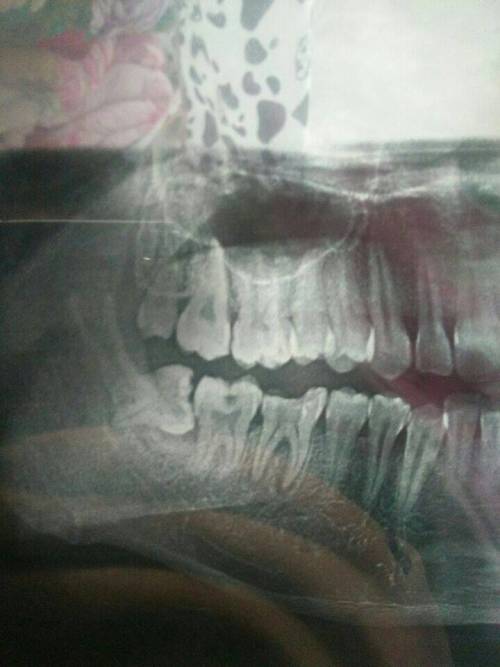

智齒是口腔中的第三大臼齒,有時候由于各種原因需要拔除,拔智齒是一項復(fù)雜的手術(shù),需要專業(yè)的牙醫(yī)進(jìn)行操作,許多人在考慮拔智齒時,最關(guān)心的問題之一就是拔智齒要花多少錢,本文將詳細(xì)解析拔智齒的費用及相關(guān)因素。

拔智齒的費用因多種因素而異,包括智齒的位置、手術(shù)的復(fù)雜性、地區(qū)差異、醫(yī)院等級以及牙醫(yī)的專業(yè)水平等,拔智齒的費用在幾百到幾千元不等,以下是拔智齒費用的具體因素:

1、智齒位置:智齒的位置是影響拔除費用的重要因素之一,智齒的位置越深,手術(shù)難度越大,拔除費用也就越高。

2、手術(shù)復(fù)雜性:拔智齒手術(shù)的復(fù)雜性也會影響費用,如果智齒生長位置正常,手術(shù)相對簡單;如果智齒被埋在骨頭里,需要切開牙齦和骨頭,手術(shù)難度增大,費用相應(yīng)增加。

1、術(shù)前檢查:拔智齒前需要進(jìn)行口腔檢查、X光片等檢查,以了解智齒的位置和周圍結(jié)構(gòu),這些檢查費用也是拔智齒總費用的一部分。